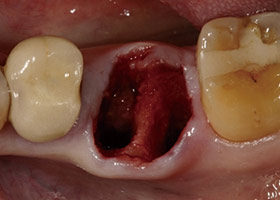

經X光片發現牙齒底部病變,評估建議立即拔牙且立即植牙